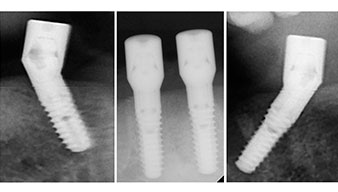

Angled abutments (35°) were screwed in to compensate for the divergence of the distal implants, with the result that the emergence profile of all implants was as perpendicular as possible to the bite plane. This is a prerequisite for occlusal placement of the provisional and subsequently the permanent denture (Fig. 15 and 16).

Implants

Fig. 15

Fig. 16

Following the time required for the osseointegration, the final impression of the implants could be performed and the final denture produced accordingly (Fig. 19 and 20). At this point, the dentist and patient were able to decide together whether to use a ceramic or acrylic veneer and a zirconium or metal framework. In this case, Dr. Pascu’s team decided on an acrylic veneer based on the unclear prognosis for the maxillary dentition and the fact that tooth 24 is elongated. This type of veneer is generally considerably easier to adapt and can thus be subsequently altered to reflect the new situation in the maxilla.

Osseointegration

Fig. 19

Fig. 20